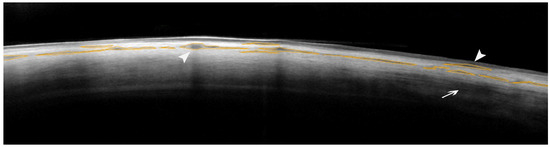

AS-OCT of the Sclera